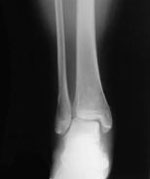

X線所見:正面像で脛骨下端部の骨折が認められ、末梢骨片は後外方へ転位していた。中枢骨片側面像では前下方への転位を認めた。腓骨は下端部で斜骨折を確認したが、転位は認めなかった

(図1)。

レントゲン側面像。

脛骨下端部に骨折線を認める。 |

レントゲン正面像。

腓骨下端部に骨折線を認める。 |